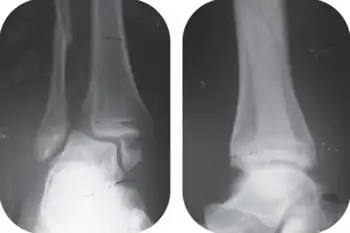

A bimalleolar fracture is a fracture of the ankle that involves the lateral malleolus and the medial malleolus. Studies have shown[1] that bimalleolar fractures are more common in women, people over 60 years of age, and patients with existing comorbidities.[1]